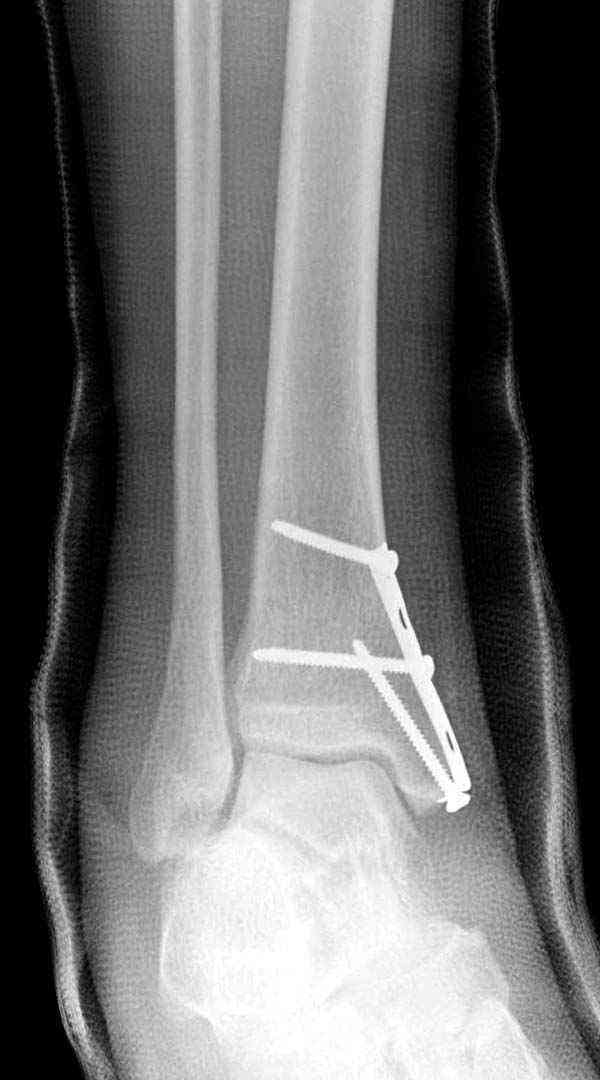

Внутренняя лодыжка

Имя     : 1 Med mal fx Hook plate 0.JPG

Имя     : 2 Med mal fx Hook plate 00.JPG

Имя     : 3 Med mal fx Hook plate 000.JPG

Имя     : 4 Med mal fx Hook plate.JPG

Имя     : 8 Med mal fx Hook plate mortise.jpg

Имя     : 9 Med mal fx Hook plate.JPG

Имя     : 10 Med mal fx Hook plate.jpg